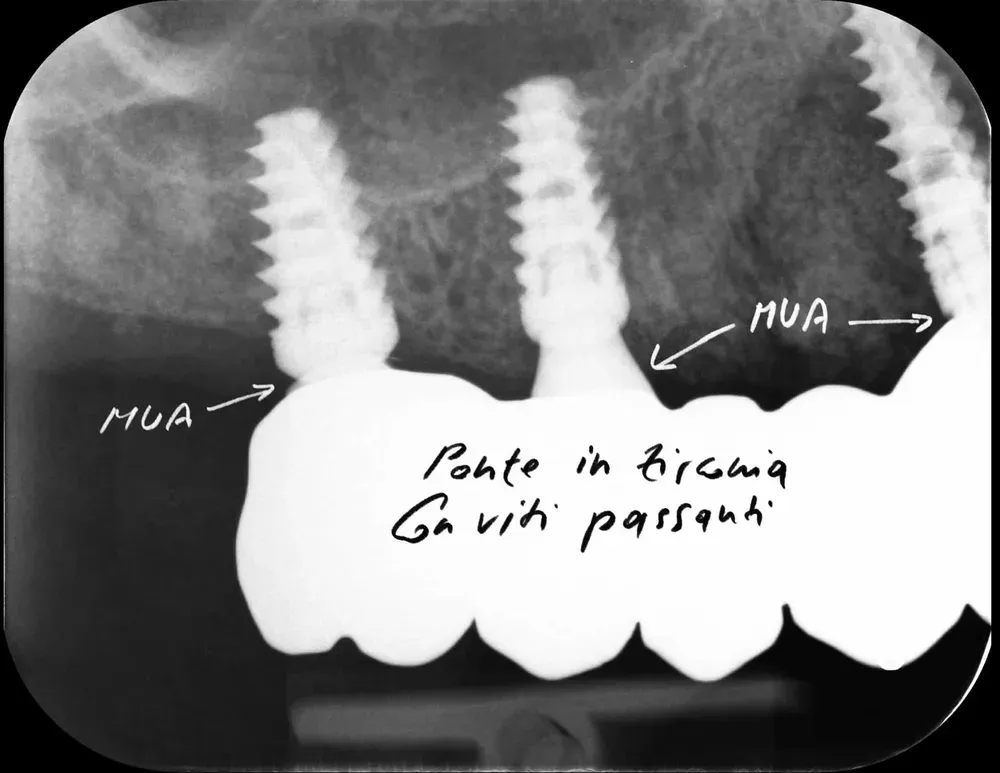

Ponti e full-arch: l’obbligo dei Multi-Unit Abutment

Nelle riabilitazioni complesse — ponti estesi, full-arch (arcate complete) — l’uso dei Multi-Unit Abutment (MUA) non è un’opzione. È una necessità clinica nella maggioranza dei casi, con l’eccezione degli impianti dritti ad esagono esterno. È particolarmente importante per tutte le connessioni interne, e in modo assoluto per le coniche. Ed è necessario anche se gli impianti sono dritti, mentre per i “tilted” (impianti inclinati) sarebbe addirittura impossibile riuscire a realizzare una qualsiasi protesi, anche imprecisa, senza i MUA.

I MUA risolvono tre problemi in un colpo. Eliminano le tensioni meccaniche durante l’inserimento delle strutture, evitando stress sull’osso crestale. Garantiscono il sigillo biologico seguendo il principio one abutment-one time: l’abutment transmucoso viene posizionato una sola volta. E spostano l’interfaccia protesica in zona coronale, più accessibile all’igiene e fuori del complesso sovracrestale. .

Il principio one abutment-one time (Luigi Canullo (2010) https://pubmed.ncbi.nlm.nih.gov/21180681/) è geniale. Abrahamsson e collaboratori nel 1997 hanno dimostrato sui beagle che la disconnessione ripetuta dell’abutment compromette la barriera mucosale e causa riassorbimento osseo aggiuntivo (https://doi.org/10.1111/j.1600-051x.1997.tb00230.x). La meta-analisi più recente di Vatėnas e Linkevičius ha quantificato il danno: 0,4 mm di perdita ossea marginale in più nel gruppo con disconnessioni ripetute (https://pubmed.ncbi.nlm.nih.gov/34528906/). Può sembrare poco. Ma in un contesto dove ogni decimo di millimetro conta per la sopravvivenza a lungo termine, è un costo evitabile.

Mi dispiace ammetterlo, ma inizialmente ero contrario ai MUA e li volevo evitare quando riuscivo a non usare impianti tilted nei full-arch. Sbagliavo. Nelle arcate complete, e spesso anche nei ponti più corti, i MUA sono indispensabili. L’alternativa è usare impianti dritti con connessione a esagono esterno — che trasforma il problema in una soluzione efficace. Oppure interporre i MUA per convertire l’esagono interno in esterno. In entrambi i casi, la biologia ci chiede di minimizzare le disconnessioni.